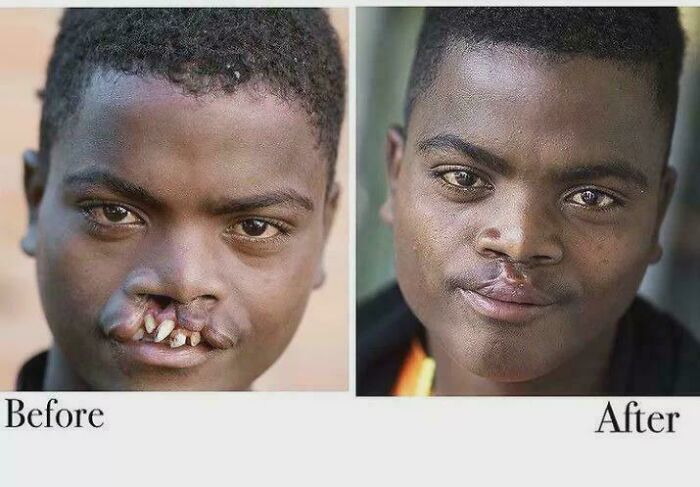

Before And After Surgery For Blount's Disease